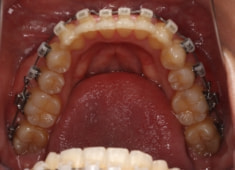

治療開始時